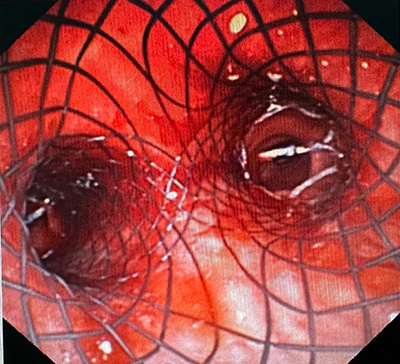

支气管镜可见中央气道Ⅰ区狭窄30%;中央气道Ⅱ区狭窄95%

由于W先生病情危重,难以承受肌松麻醉,王洪武主任当机立断,敲定“软镜下Y形金属覆膜支架置入术”这一最优替代方案。随后,他亲自操作,团队成员全程协助,采用全麻下经口进软镜的方式开展操作,进镜后于中央气道Ⅰ区约声门下2cm处见膜部隆起致管腔狭窄约30%,中央气道Ⅱ区距隆突上5cm处外压型管腔狭窄约95%,病变长度约3cm,狭窄处气道几乎闭塞,这正是患者术前呼吸困难、无法平卧的核心原因。